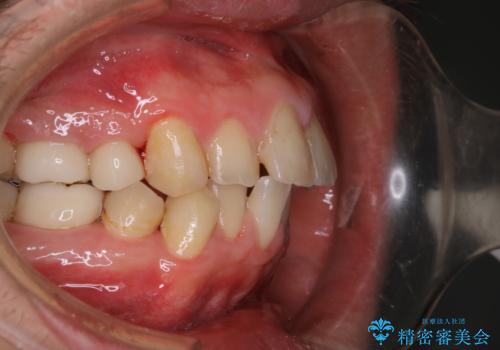

インビザライン中にステインの除去

- インビザラインでのマウスピース矯正中の方で、歯の表面のステインをきれいに取りたいとのことでした。PMTC60分コースを行いました。

PMTC(保険外治療)は、毎日の歯磨きで落としきれない汚れや、コーヒ、紅茶・タバコのヤニなどの着色も除去します。目には見えない歯と歯の間・歯肉の境目・インビザライン中はアタッチメント周囲などに残っているプラーク(歯垢)もしっかり取り除きます。PMTCでは専門的な機械や材料を使用して、徹底的に汚れを除去するため、虫歯・歯周病・口臭予防などにつながります。